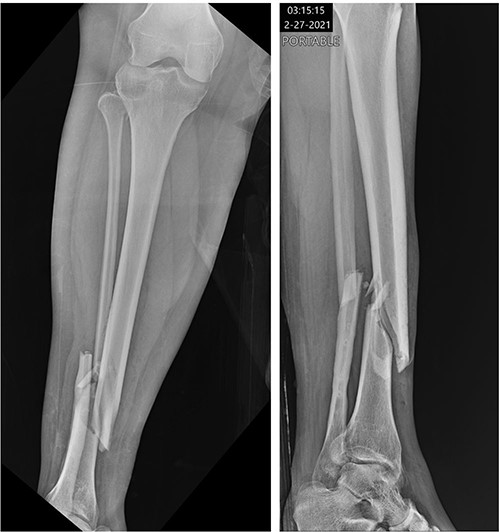

A 34-year-old obese female (body mass index of 48.17 mg/kg2) presented to a level 1 trauma center after experiencing a ground level fall and sustaining a displaced Gustilo-Anderson grade 1 open comminuted spiral fracture of the right distal tibial shaft (OTA classification 42A1c) (Fig. 1). Other injuries included a displaced comminuted distal fibula fracture and a nondisplaced proximal fibular neck fracture. In the emergency department, the 1.5 cm wound over the distal anteromedial tibia was irrigated with 3 L of normal saline, and the fracture was reduced and splinted.

Initial radiographs demonstrating fractures of the proximal fibular neck and distal tibia and fibula.